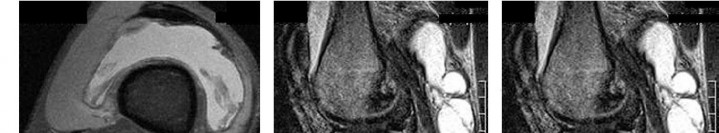

Question 18

A 60-year-old male presents with isolated medial compartment knee osteoarthritis and is being evaluated for a unicompartmental knee arthroplasty (UKA). According to classical indications (Kozinn and Scott), which of the following is considered an absolute contraindication to a fixed-bearing UKA?

Explanation

Classical criteria for unicompartmental knee arthroplasty (UKA) include an intact anterior cruciate ligament (ACL). ACL deficiency leads to altered knee kinematics, specifically paradoxical anterior translation of the tibia during flexion, which results in accelerated posterior polyethylene wear and early failure of a fixed-bearing UKA. While some modern surgeons perform UKA in ACL-deficient knees using mobile-bearing designs or concurrent ACL reconstruction, an absent ACL remains a classic board-tested contraindication for standard UKA.